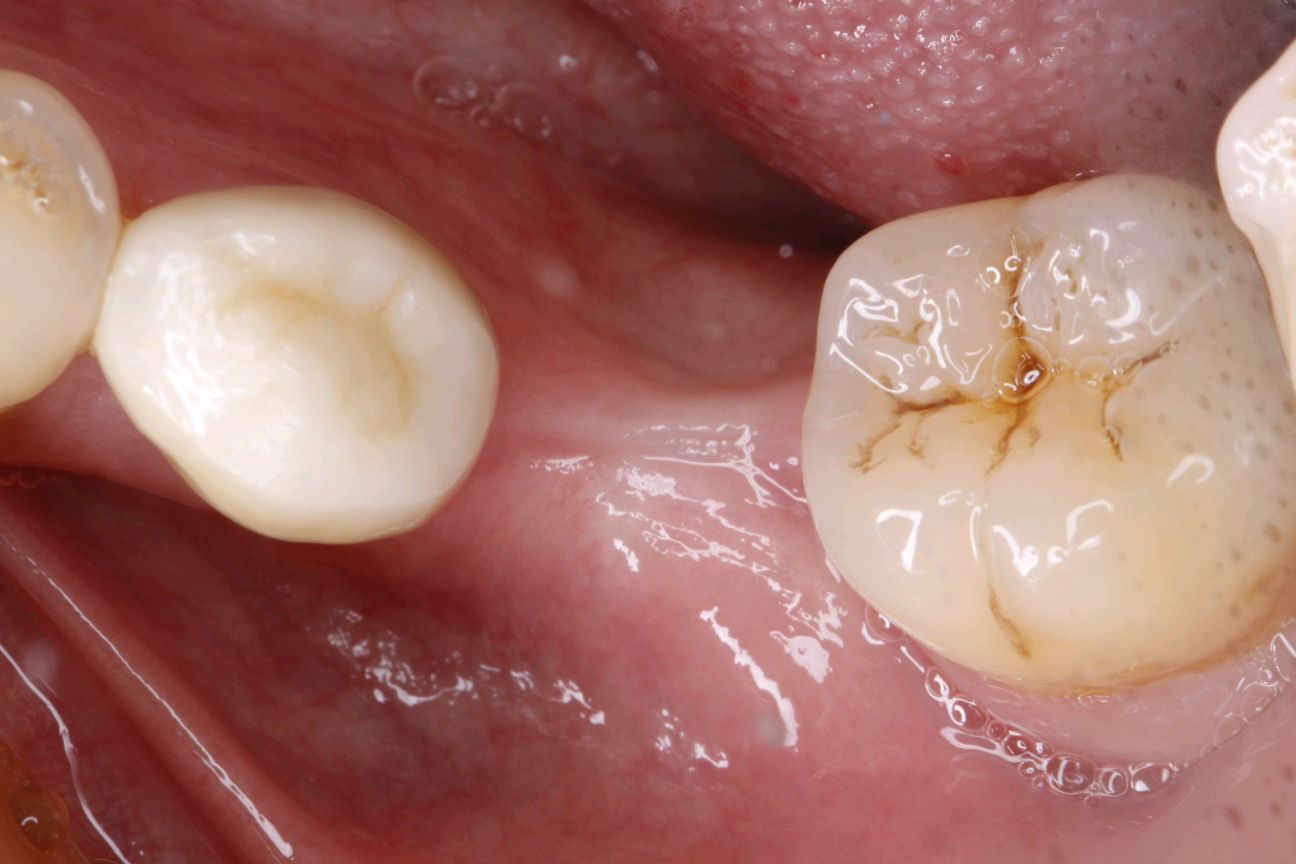

受区准备:15号刀片沿着膜龈联合联合部位做,深为1mm的水平切口,向根方组织充分锐性分离

供区制备:第一前磨牙与第一磨牙近中根,距牙龈边缘2mm处制作非全厚切口,获得一个上皮组织瓣。

缝合完成移植瓣与受区骨膜的固定。确保无松动。

牙周塞治剂涂抹创面。佩戴腭护板